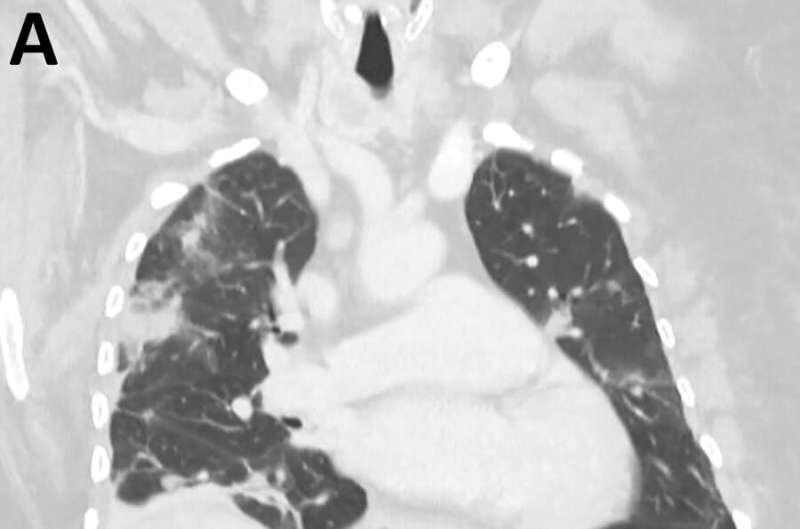

По мнению исследователей, женщина из Австралии, вероятно, заразилась круглым червем после сбора местной травы возле озера для своего питона. Пациентка также использовала эту зелень для приготовления пищи, поэтому существует вероятность, что она заразилась паразитом непосредственно при прикосновении или употреблении травы. Симптомы заболевания появились у пациентки еще в январе 2021 года. "Вначале у нее появились боли в животе и диарея, затем лихорадка, кашель и одышка. В ретроспективе эти симптомы, скорее всего, были связаны с миграцией личинок круглых червей из кишечника в другие органы, такие как печень и легкие. Были взяты дыхательные пробы и проведена биопсия легких, однако в этих пробах паразиты не были обнаружены", - сказала Карина Кеннеди, принимавшая участи в извлечении паразита. "В то время попытка идентифицировать личинки, которые ранее не были признаны причиной заражения человека, была сродни попытке найти иголку в стоге сена. В 2022 году у пациентки начались едва заметные изменения памяти и мышления, и ей была проведена МРТ головного мозга, которая показала атипичное поражение правой лобной доли мозга."

Впервые австралийка была госпитализирована в конце января 2021 г после трехнедельных болей в животе и диареи, сопровождавшихся постоянным сухим кашлем, повышением температуры и потливостью. К 2022 г у нее появились забывчивость и депрессия, что послужило поводом для проведения МРТ. Нейрохирурги исследовали аномалии, и именно тогда обнаружили восьмисантиметрового круглого червя. Позже его идентичность была подтверждена паразитологами, сначала по внешнему виду, а затем и с помощью молекулярных исследований.